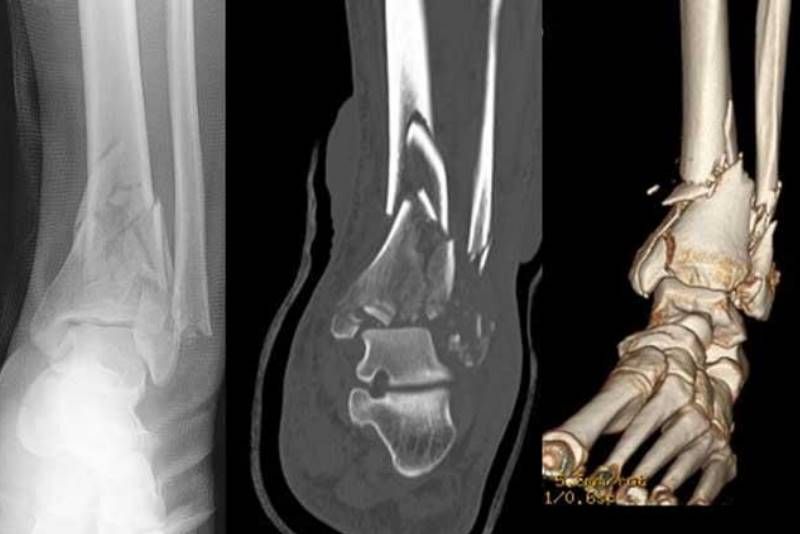

Ανεξάρτητα εάν η κλινική διάγνωση είναι βέβαιη ή όχι, ο ακτινολογικός έλεγχος είναι πάντα απαραίτητος για να επιβεβαιωθεί η ύπαρξη του κατάγματος και να προσχεδιαστεί ή θεραπεία.

Επί αμφιβολίας ή αδυναμίας του ακτινολογικού ελέγχου την διάγνωση μπορεί να συμπληρώσει με εξαιρετική ακρίβεια η αξονική τομογραφία.

Με την αξονική τομογραφία η διάγνωση του κατάγματος παρέχεται με μεγαλύτερη ακρίβεια συγκριτικά με άλλες απλές απεικονιστικές μεθόδους. Κατά τη διάρκεια της εξέτασης ο αξονικός τομογράφος διαιρεί το σώμα σε εγκάρσιες τομές τις οποίες και απεικονίζει σε ψηφιακή μορφή. Οι τομές αυτές είναι πάχους ενός χιλιοστού.

Οι αξονικές τομογραφίες αποτελούν πολυδιάστατα διαγνωστικά εργαλεία στα χέρια των κλινικών ιατρών.

Μπορούν να δημιουργήσουν για παράδειγμα μια τρισδιάστατη εικόνα ενός κατάγματος καθώς η κάμερα ενός αξονικού τομογράφου κάνει έναν ολοκληρωμένο κύκλο γύρω από την περιοχή ενδιαφέροντος, τραβώντας μερικές χιλιάδες ακτινογραφίες. Η τρισδιάστατη απεικόνιση έχει ιδιαίτερη αξία στα κατάγματα καθώς καταγραφεί με ευκρίνεια την περιοχή ενδιαφέροντος και εφοδιάζει τον χειρουργό με πληροφορίες ώστε να γίνει ο απαραίτητος προεγχειρητικός σχεδιασμός.